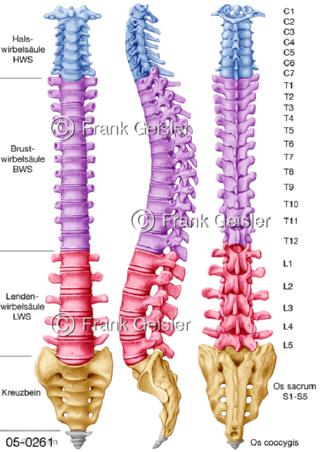

Bildergalerie Skelettsystem

Bilder zum Skelettsystem zeigen die Stützstruktur des menschlichen Körpers, die Knochen, eine besonders harte Form des Bindegewebes und Stützgewebes, welche das menschliche Skelett bildet, die Knochen des Stammes, der Extremitäten sowie der Gelenke